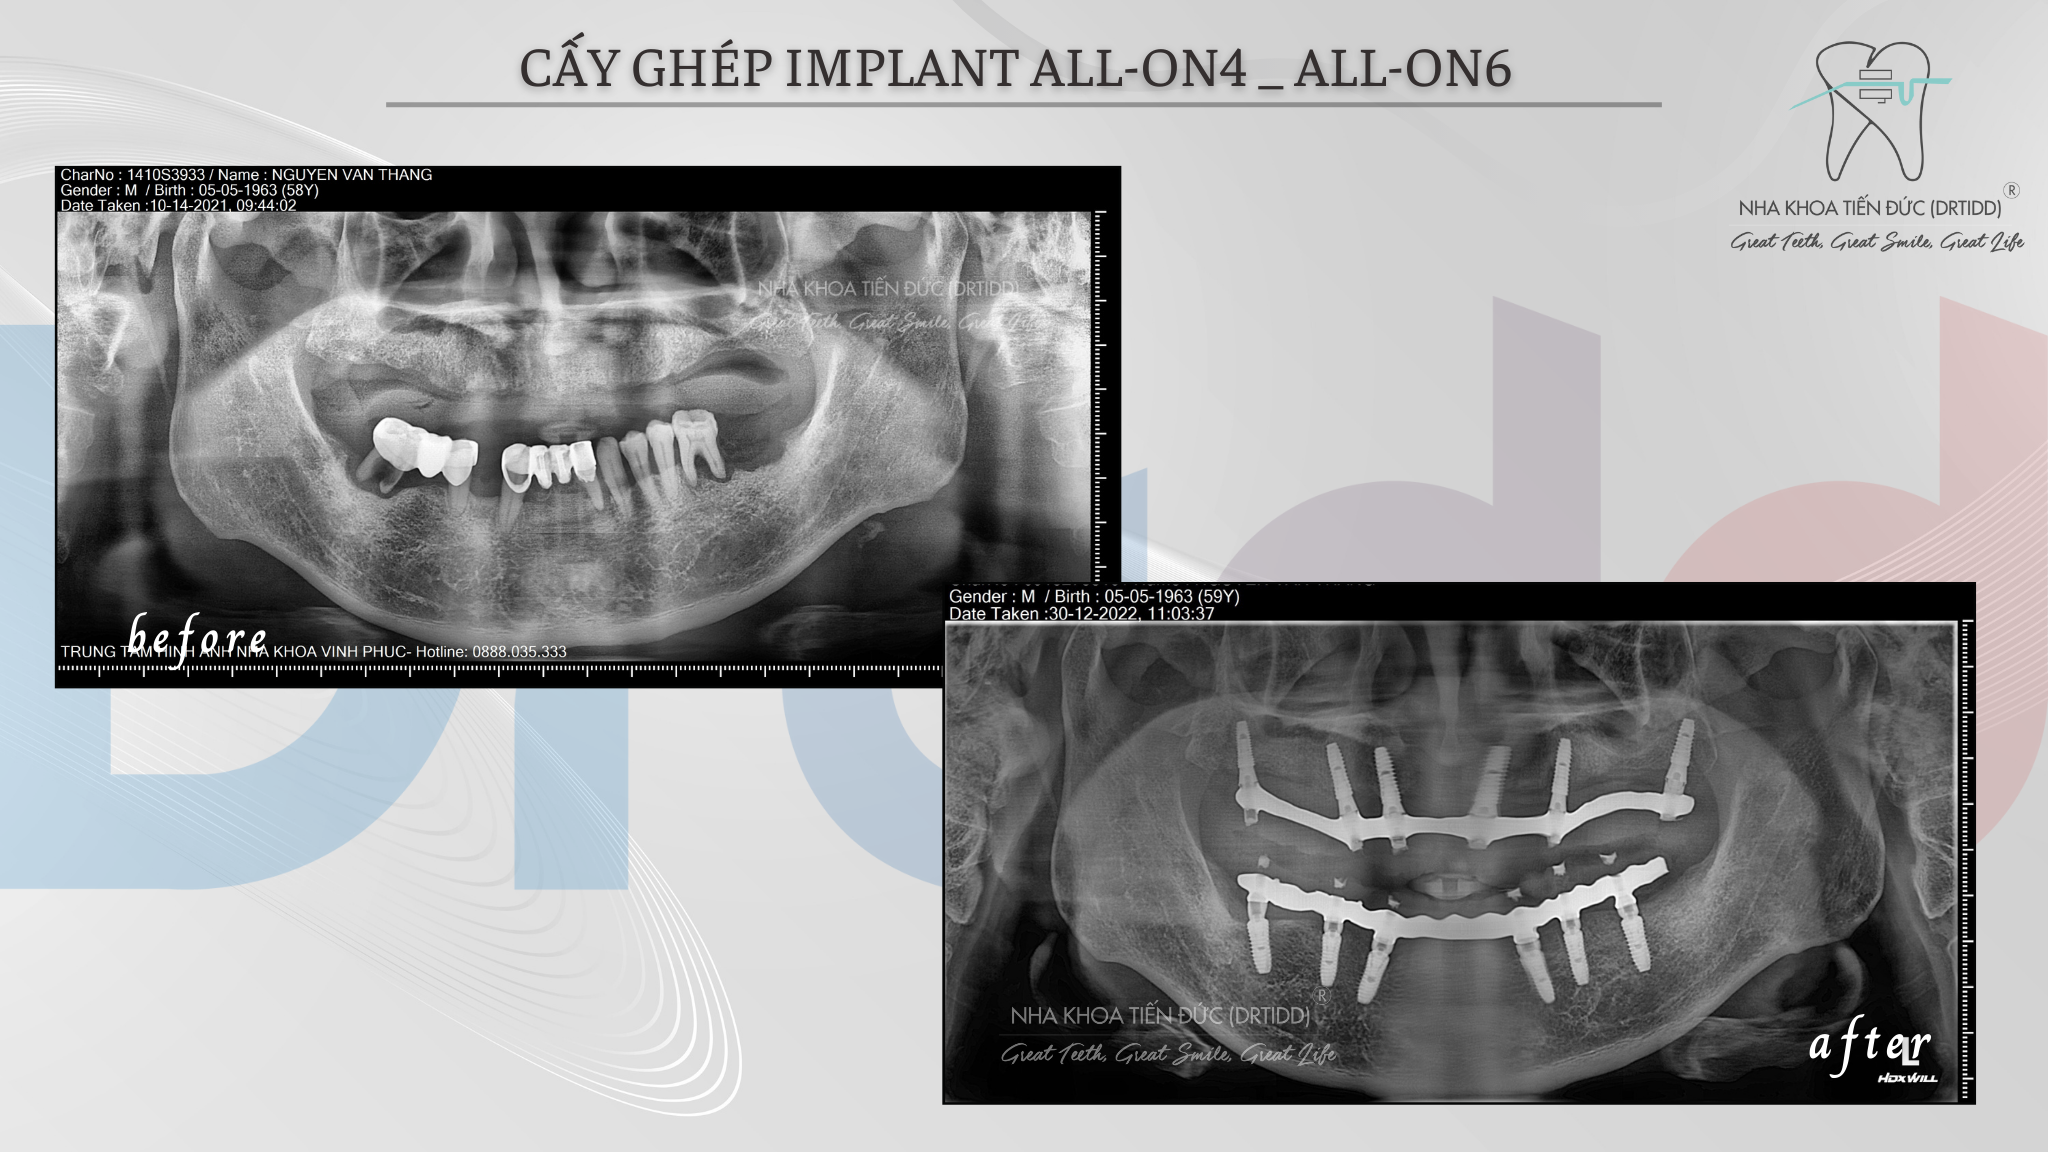

Bệnh nhân sẽ được khám răng miệng tổng quát, chụp ảnh và chụp phim, chụp CTCB cắt lớp để chuẩn đoán tình trạng răng và xương chính xác, đầy đủ.

Sau khi chẩn đoán được tình trạng răng miệng bệnh nhân, bác sĩ sẽ lên phác đồ điều trị cụ thể, dựa vào thể tích và cấu trúc xương hàm, tình trạng răng và khớp cắn, bác sĩ sẽ lựa chọn 4-6 trụ implant phù hợp nhất